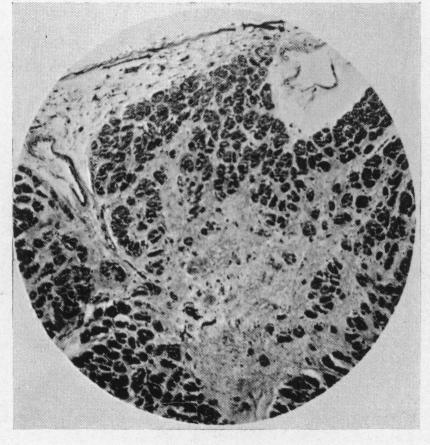

Fibro-elastosis of the heart in adolescence.

Br Heart J. 1957 Apr;19(2):186-92. doi: 10.1136/hrt.19.2.186.